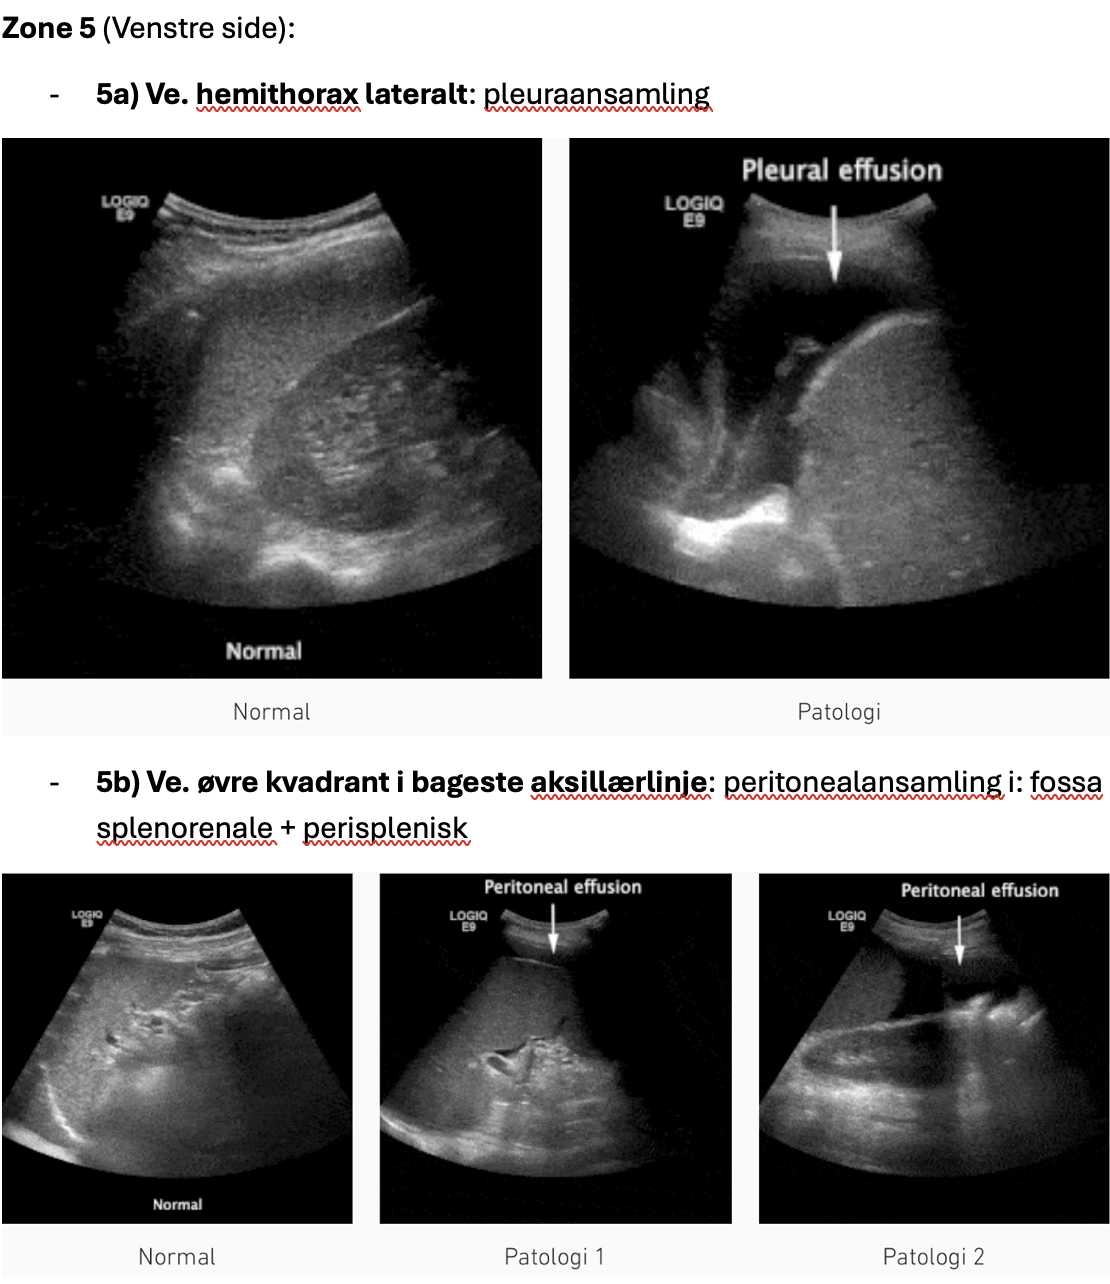

- 5a) Ve. hemithorax lateralt: pleuraansamling

- 5b) Ve. øvre kvadrant i bageste aksillærlinje: peritonealansamling i: fossa splenorenale + perisplenisk